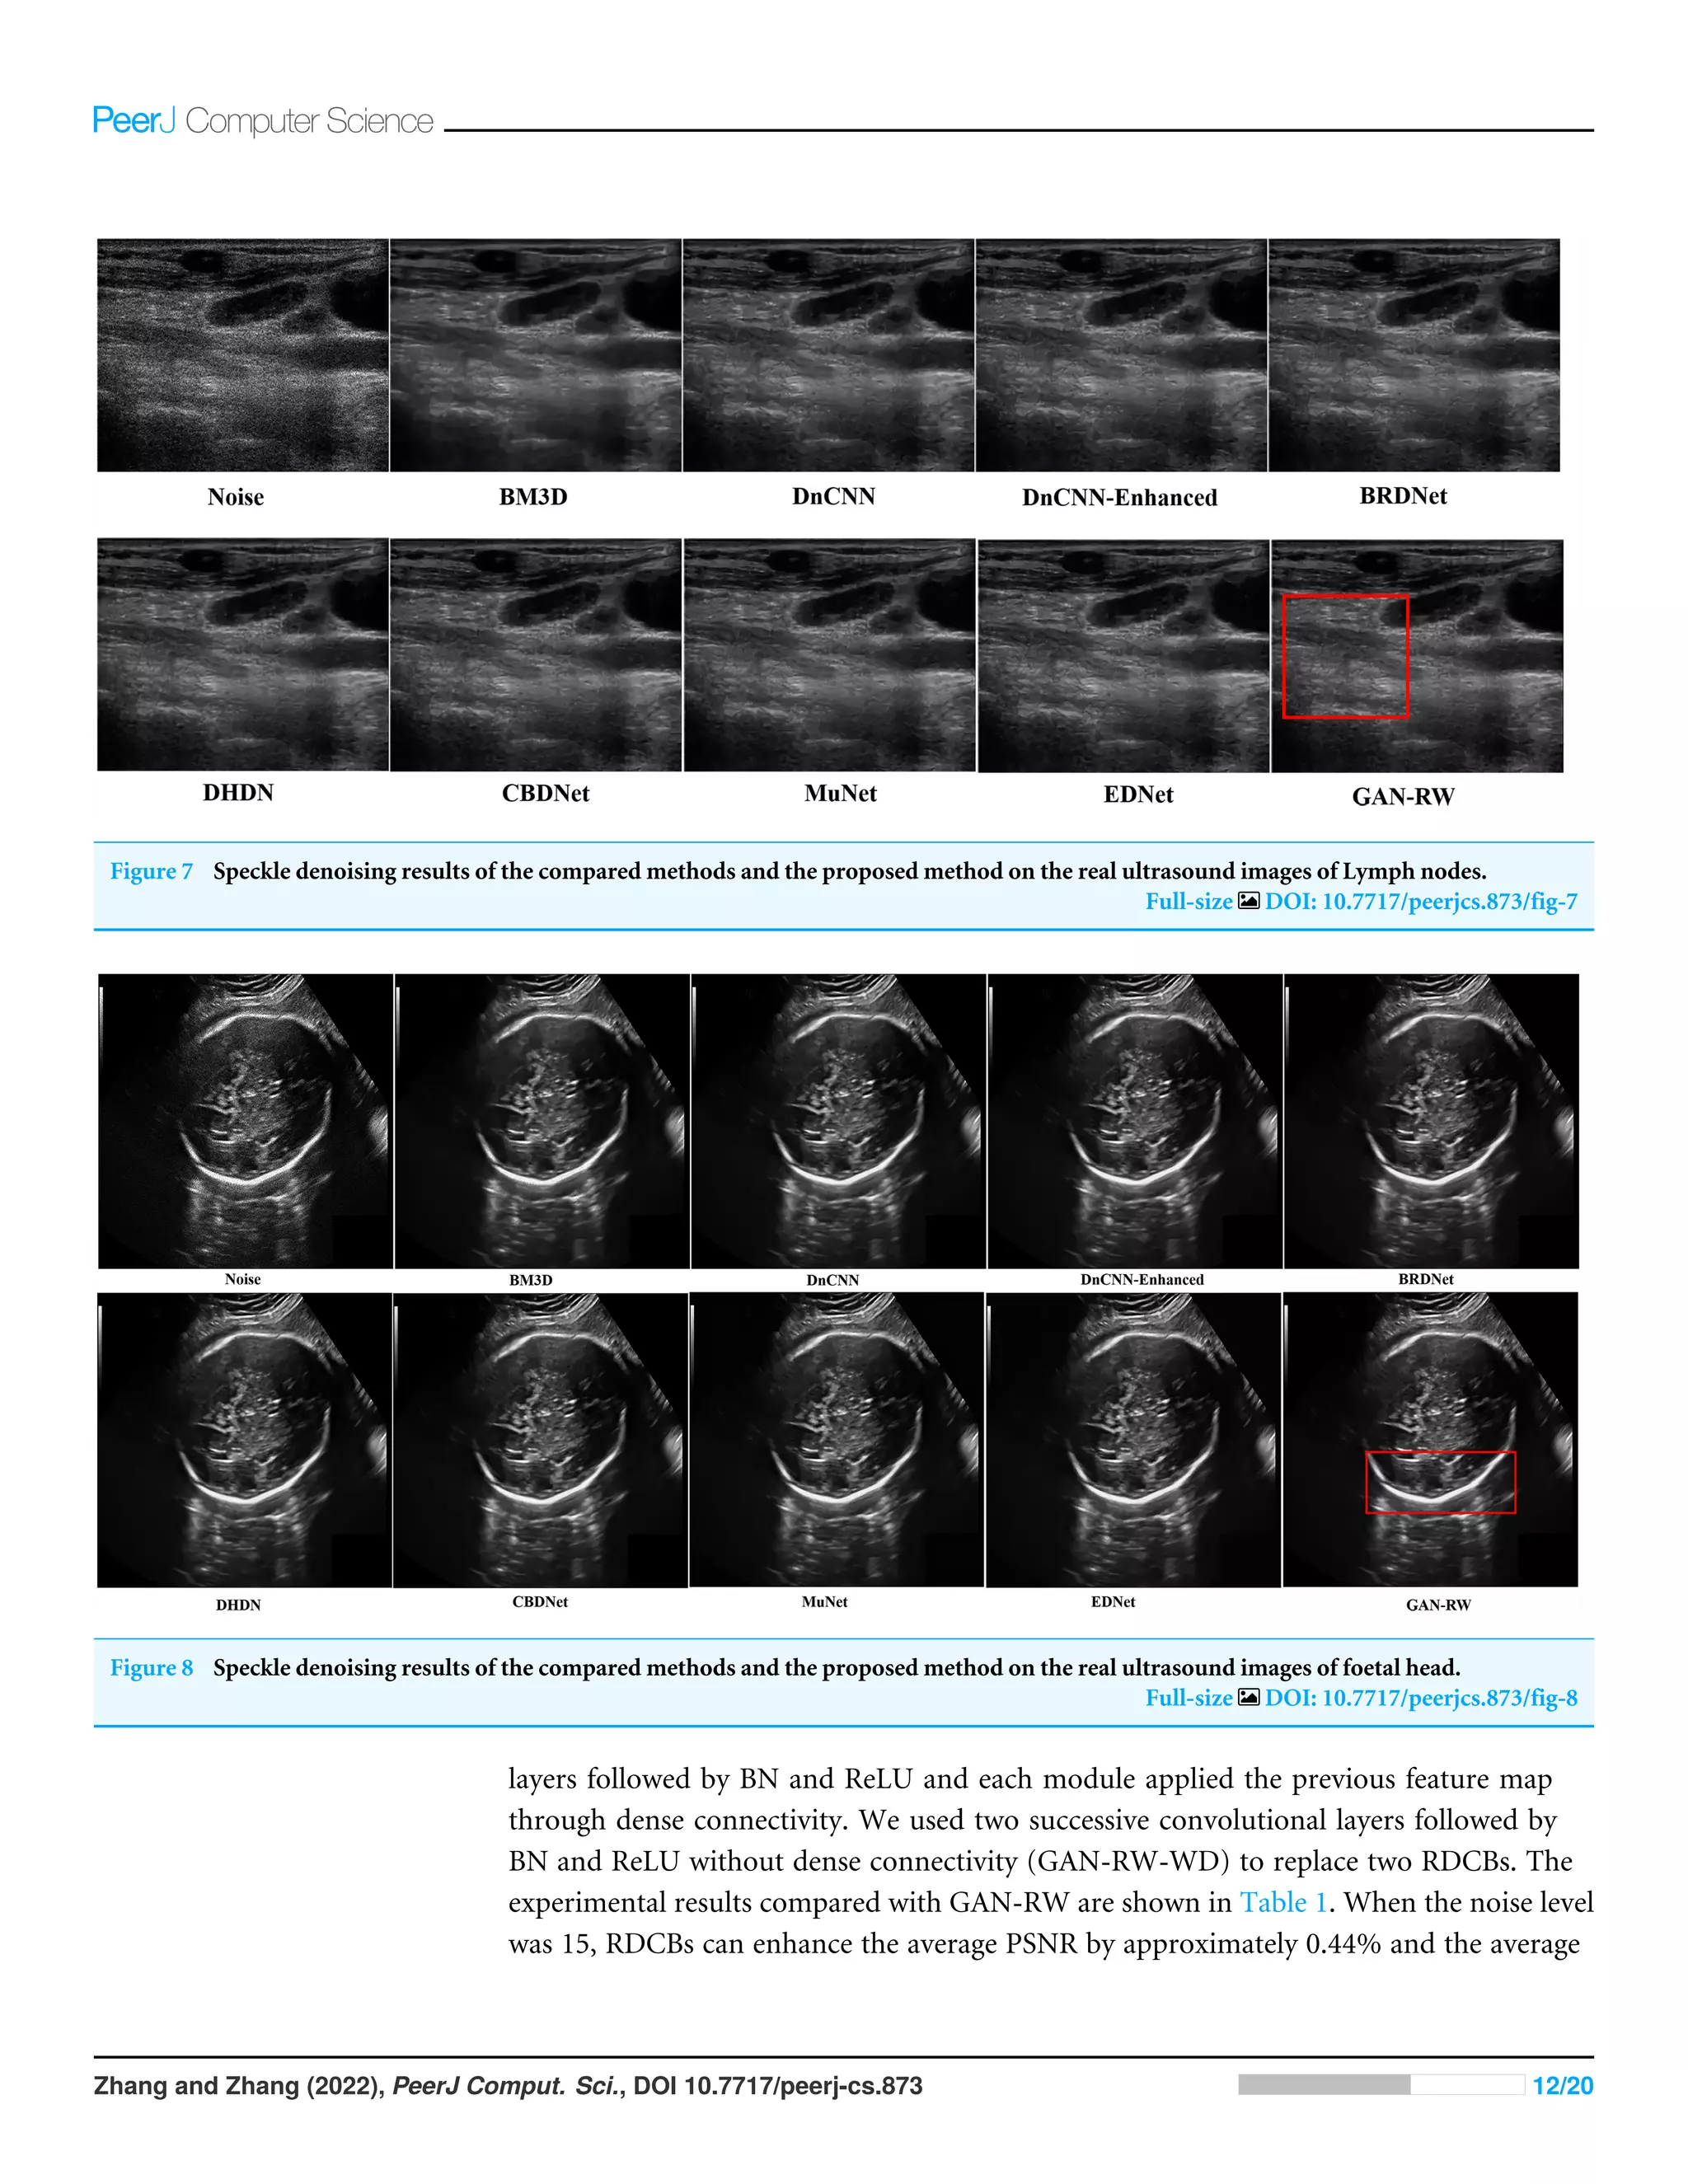

with red box in the figure. Figure 7 shows the despeckling images of different methods

and improving the subjective visual effect.

In addition, other foetal ultrasound images were applied to visually compare the

despeckling performance of all evaluated methods. In Fig. 8, it is easy to observe that our

proposed algorithm produced a smoother outline and retained the image details better

than the other methods.

Figure 7 Speckle denoising results of the compared methods and the proposed method on the real ultrasound images of Lymph nodes.

Full-size DOI: 10.7717/peerjcs.873/fig-7

Figure 8 Speckle denoising results of the compared methods and the proposed method on the real ultrasound images of foetal head.

Full-size DOI: 10.7717/peerjcs.873/fig-8